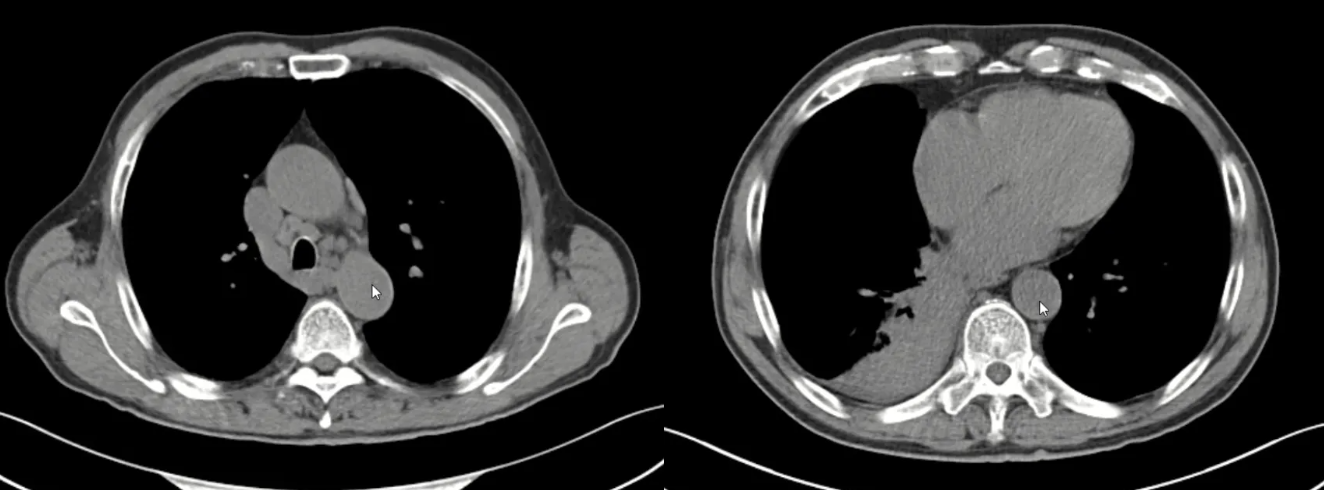

影像学(治疗后1个月,2025年8月28日CT):右肺下叶阻塞性肺炎显著吸收,实变范围缩小;纵隔及肺门肿大淋巴结明显缩小;右侧胸腔积液基本完全吸收。对比治疗前后CT,变化一目了然,充分证实了病变对免疫抑制治疗的敏感性。

图4:激素治疗1月后复查肺部CT

血清学标志物:IgG4水平成为监测疾病活动的良好指标。从治疗前的4.24 g/L,稳步下降至2.20 g/L(2025年8月)→ 1.25 g/L(2025年9月)→ 0.78 g/L(2025年11月,已接近正常)。

血小板计数:也随着炎症控制而逐渐回升至正常范围。